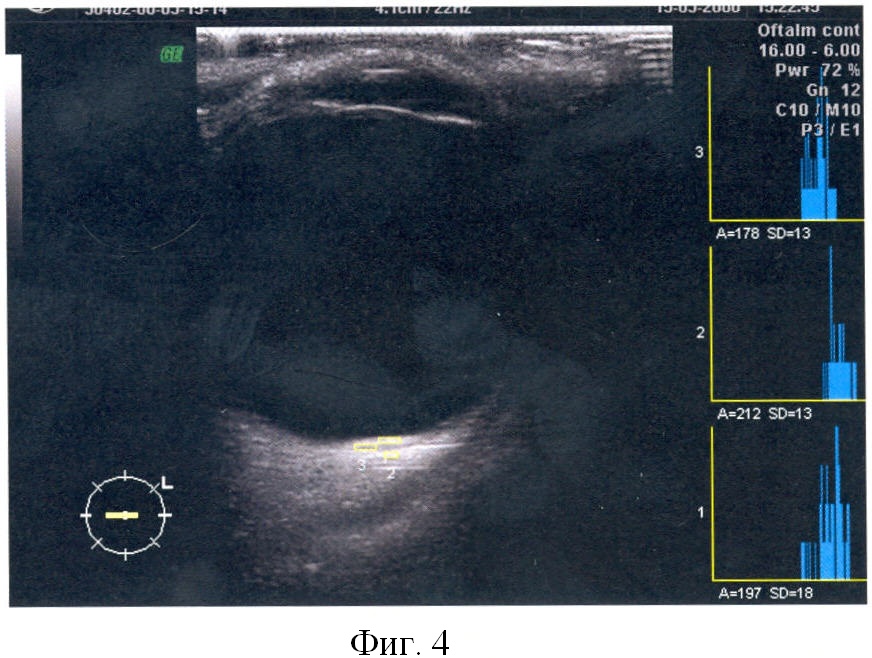

На фигуре 1 показано двухмерное сканирование субретинальной неоваскулярной мембраны с определением показателей плотности патологического очага в двухмерном режиме.

А1 – 59

А2 – 81

А3 – 195

K2D=(A1+A2)/A3=0,7

K2D=0,7